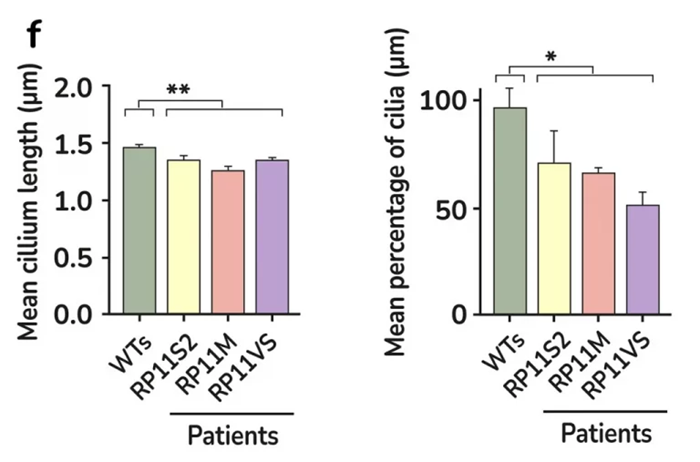

Quantification of cilia length and frequency in photoreceptors showing significant reduction in RP11 patients compared to the controls. Image Credit: Newcells Biotech

After creating retinal organoids from RP Type 11 patients with a mutation in the pre-mRNA processing factor 31 (PRPF31), the mechanism behind the retinal dysfunction in this disease has been clarified.

Large-scale transcriptome analyses that revealed patient-specific and cell type-specific mis-splicing of PRPF31 target genes impacted by PRPF31 mutations made unprecedented molecular characterization of splicing-factor RP clinical phenotypes possible.

This study uncovered several cellular defects, including progressive cellular degeneration, altered cilia morphology in photoreceptors, dysfunctional RPE, and cellular stress, as demonstrated by phenotypic rescue. The study was the first to use patient-derived organoids, or RPEs, to demonstrate the cellular phenotypes linked to RP.

This research and expertise were developed in the lab of Prof. Lako, a co-founder of Newcells Biotech and a professor of stem cell sciences at Newcastle University’s Biosciences Institute, Faculty of Medical Sciences.